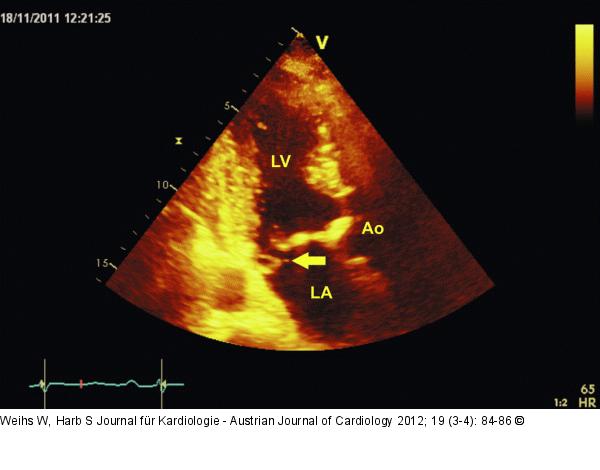

Abbildung 1: Apikaler Längsschnitt Apikaler Längsschnitt. Aortenklappensklerose mit visuell höchstens gering eingeschränkter Öffnungsfunktion. Degenerativ veränderte Mitralklappe mit Prolaps und partiellem „flail leaflet“ des posterioren Segels (Pfeil). LV: linker Ventrikel; LA: linker Vorhof; Ao: Aorta |

Apikaler Längsschnitt. Aortenklappensklerose mit visuell höchstens gering eingeschränkter Öffnungsfunktion. Degenerativ veränderte Mitralklappe mit Prolaps und partiellem „flail leaflet“ des posterioren Segels (Pfeil). LV: linker Ventrikel; LA: linker Vorhof; Ao: Aorta |